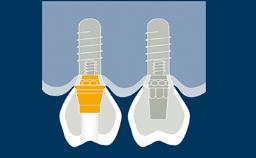

As próteses provisórias desempenham um papel importante na substituição de dentes perdidos durante a terapia com implantes, até o ponto em que os implantes estão prontos para serem restaurados. A terapia com implantes geralmente envolve vários estágios clínicos e laboratoriais, e as próteses provisórias buscam garantir que o paciente esteja confortável em um nível estético e funcional durante toda a duração do tratamento. As próteses provisórias também têm importantes funções diagnósticas e podem ser um fator-chave para alcançar a satisfação do paciente com o resultado definitivo do tratamento. Existem várias opções de próteses provisórias, fixas e removíveis.